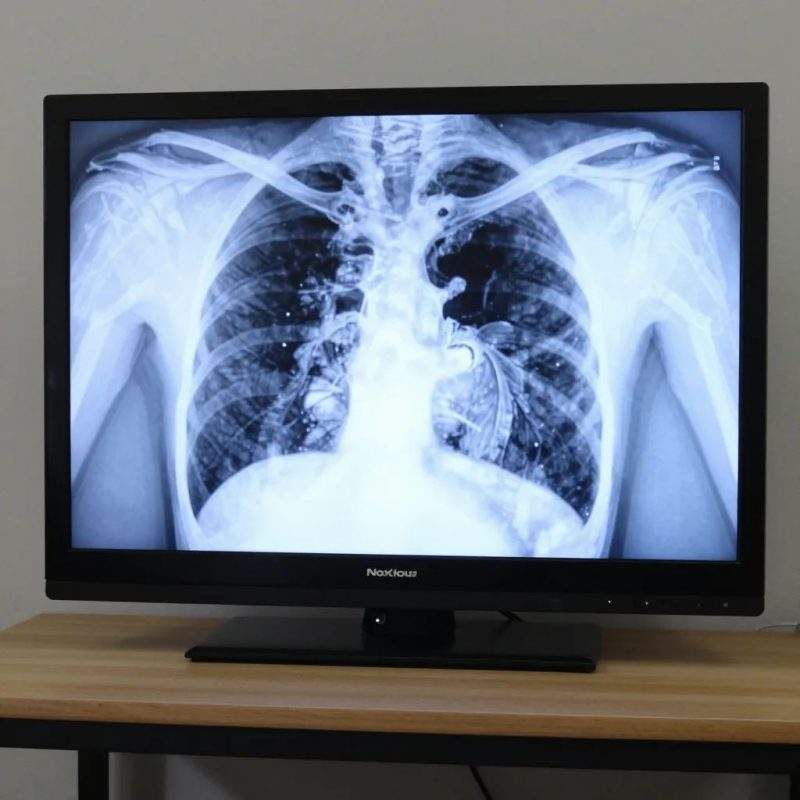

Kad pacientam tiek diagnosticēta plaušu fibroze, dažkārt profesors Alvils Krams spēj atrast slimības cēloni. Viņš pēta detalizētas plaušu rentgenogrammas, raugās augstas izšķirtspējas datortomogrāfijas attēlos, nereti izmanto plaušu biopsiju. Bet ja viņš vai viņa kolēģes nevar atrast plaušu fibrozes iemeslu, viņi fibrozi mēdz saukt par „idiopātisku”. Vārds „idiopātisks” nozīmē „nezināmas cēloņsakarības”.

Diagnostikai ārsti lieto plaušu funkcionālos testus, krūšu kurvja rentgenogrāfiju, asins bioķīmiskās analīzes un augstas izšķirtspējas datortomogrāfiju. Man šķiet, ka bez rentgenogrāfijas var iztikt un uzreiz pacientu sūtīt uz datortomogrāfiju. Dažreiz ir nepieciešama papildu informācija, un var tikt veikta plaušu biopsija.

Augstas izšķirtspējas datortomogrāfija parāda plaušu audu sīkās detaļas. Datortomogrāfijā veseli plaušu audi izskatās gandrīz melni, bet rētas un iekaisumi izskatās pelēki vai balti.